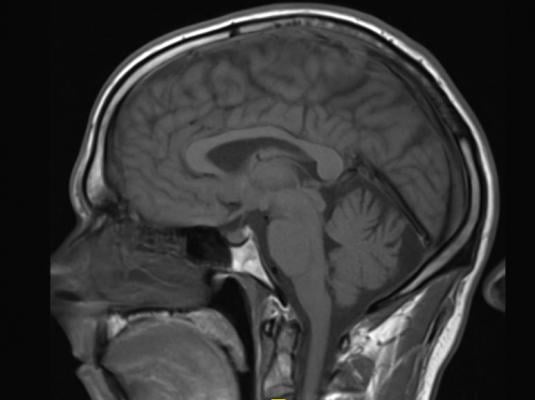

December 31, 2020 — Posttraumatic stress disorder (PTSD) is a complex psychiatric disorder brought on by physical and/or psychological trauma. How its symptoms, including anxiety, depression and cognitive disturbances arise remains incompletely understood and unpredictable. Treatments and outcomes could potentially be improved if doctors could better predict who would develop PTSD. Now, researchers using magnetic resonance imaging (MRI) have found potential brain biomarkers of PTSD in people with traumatic brain injury (TBI).

"MRI studies conducted within two weeks of injury were used to measure volumes of key structures in the brain thought to be involved in PTSD," said Stein. "We found that the volume of several of these structures were predictive of PTSD 3-months post-injury."

Specifically, smaller volume in brain regions called the cingulate cortex, the superior frontal cortex, and the insula predicted PTSD at 3 months. The regions are associated with arousal, attention and emotional regulation. The structural imaging did not predict PTSD at 6 months.

The findings are in line with previous studies showing smaller volume in several of these brain regions in people with PTSD and studies suggesting that the reduced cortical volume may be a risk factor for developing PTSD. Together, the findings suggest that a "brain reserve," or higher cortical volumes, may provide some resilience against PTSD.